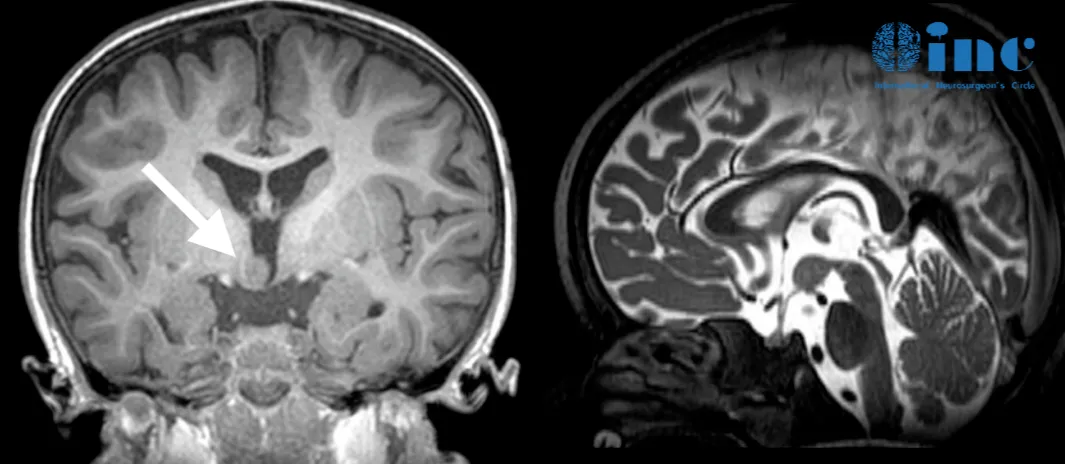

2岁的俊俊父母发现孩子总是不受控制似的做鬼脸,发出痴笑的表情,并且频率一天比一天高。

神经系统检查和核磁共振检查结果提示:颅内下丘脑错构瘤致使痴笑样癫痫发作。服用药用治疗后,痴笑样癫痫依然无法控制,只有手术切除孩子颅内的下丘脑错构瘤才能真正治好孩子的癫痫症状。

然而他们担心开颅手术会造成并发症,而且孩子年纪较小,术后护理难度更大。在多方打听后他们找到了INC加拿大Rutka教授,决定咨询教授是否有不开颅就能消融俊俊下丘脑错构瘤的办法。Rutka教授回复可以为俊俊实行LITT消融病灶。

Rutka教授及其团队做了非常充分的准备,LITT利用的是先进的磁共振成像MRI引导技术,可以清晰地识别病灶与周围健康脑组织的位置关系,进而制定精确的手术路径。